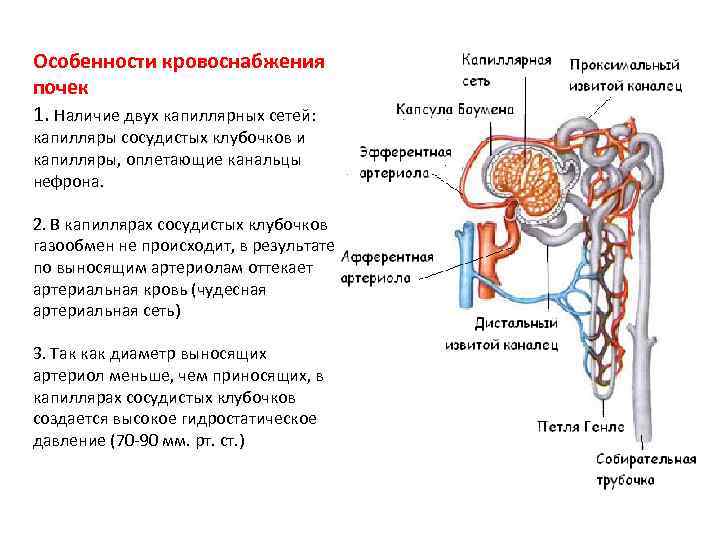

Кровоснабжение почек -Почечная артерия -Сегментарные артерии (5) -Междолевые артерии -Дуговые артерии -Междольковые артерии -Приносящие артериолы -40 -50 капиллярных петель

Кровоснабжение почек -Почечная артерия -Сегментарные артерии (5) -Междолевые артерии -Дуговые артерии -Междольковые артерии -Приносящие артериолы -40 -50 капиллярных петель

Почечное (мальпигиево) тельце состоит из капсулы клубочка (Шумлянского. Боумена) и капиллярной сети

Почечное (мальпигиево) тельце состоит из капсулы клубочка (Шумлянского. Боумена) и капиллярной сети

Особенности кровоснабжения почек 1. Наличие двух капиллярных сетей: капилляры сосудистых клубочков и капилляры, оплетающие канальцы нефрона. 2. В капиллярах сосудистых клубочков газообмен не происходит, в результате по выносящим артериолам оттекает артериальная кровь (чудесная артериальная сеть) 3. Так как диаметр выносящих артериол меньше, чем приносящих, в капиллярах сосудистых клубочков создается высокое гидростатическое давление (70 -90 мм. рт. ст. )

Особенности кровоснабжения почек 1. Наличие двух капиллярных сетей: капилляры сосудистых клубочков и капилляры, оплетающие канальцы нефрона. 2. В капиллярах сосудистых клубочков газообмен не происходит, в результате по выносящим артериолам оттекает артериальная кровь (чудесная артериальная сеть) 3. Так как диаметр выносящих артериол меньше, чем приносящих, в капиллярах сосудистых клубочков создается высокое гидростатическое давление (70 -90 мм. рт. ст. )